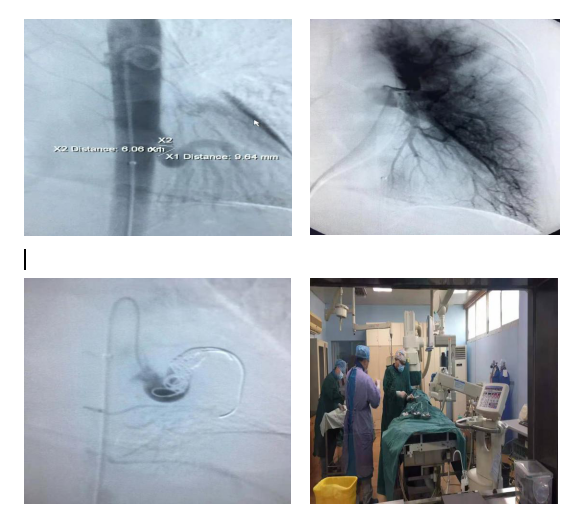

患者為一年輕女性,因咯血6天來(lái)我院就診,胸部CTA提示“左下肺基底段異常體動(dòng)脈供血”。該病是一種極少見(jiàn)的先天性疾病。經(jīng)病情分析并征求家屬同意后,行“支氣管造影術(shù)+肺動(dòng)脈造影術(shù)+異常體動(dòng)脈造影、栓塞術(shù)”。術(shù)中造影示:發(fā)自胸主動(dòng)脈的粗大血管供應(yīng)左肺下葉,S9、10段肺動(dòng)脈缺如。使用4枚cook彈簧圈對(duì)其主干進(jìn)行栓塞,復(fù)查造影示血流消失。術(shù)后隨訪該患者,無(wú)咯血、無(wú)胸痛等不適癥狀。

該手術(shù)的開(kāi)展,填補(bǔ)了我院異常體動(dòng)脈供血左下肺基底段的咯血介入手術(shù)的空白,也標(biāo)志著我院介入血管科的專業(yè)技術(shù)水平達(dá)到一個(gè)新高度。